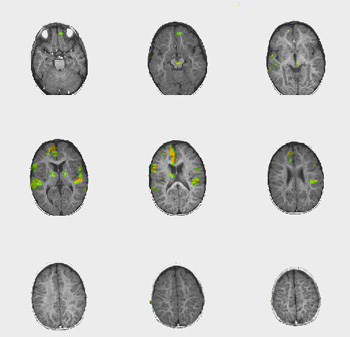

| Caso 2 |

| Paciente |

Niño de 18 meses de edad con parálisis cerebral leve. |

| Paradigma |

ACTIVADO: Presentación de la voz de la madre, pregrabada, en la que usa palabras y sonidos familiares

DESACTIVADO: Nada. Paciente sedado con propofol |

| Estadísticas |

| Método estadístico |

Valor P |

Puntuación Z |

| Prueba T |

0,0005 |

3,2 |

| Activación |

La activación de las áreas auditivas está bien definida. Se observa activación bitalámica. No se comprende claramente la fuerte activación del lóbulo frontal parasagital derecho. |